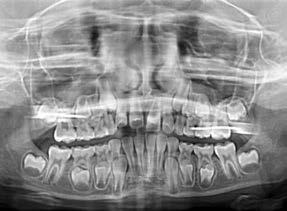

Aurélien Case treated with EF T Slim Long

Treatment time: 12 months

• Skeletal Class I • Lingual dysfunction during swallowing

• Family history (mother treated with maxillofacial surgery and father treated for impacted maxillary canines)

Before wearing EF T Slim Long

After 12 months wearing EF T